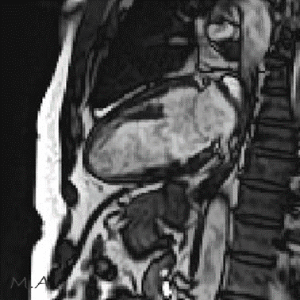

MRI

MRIとはMagnetic Resonance Imaging(磁気共鳴画像法)の略で、強力な磁石と電波を使って様々な角度から体の断面を画像化する検査です。

X線を使用しないため、放射線被ばくの心配がなく、軟部組織(筋肉、靱帯、神経など)の描出に優れており、がんの有無や広がり、転移の有無などを調べることができます。また、造影剤を用いずに血管を描出することが可能です。

部位や目的により異なりますが、検査時間は15分から40分程度です。複雑で高度な検査の場合は60分程かかる場合もあります。

当院ではCanon社製Vantage Fortian MRI 1.5Tを設置しており、主に脳血管疾患、脊椎疾患、閉塞性動脈硬化症などの下肢疾患、腹部疾患、心臓疾患、関節等の検査を行っています。